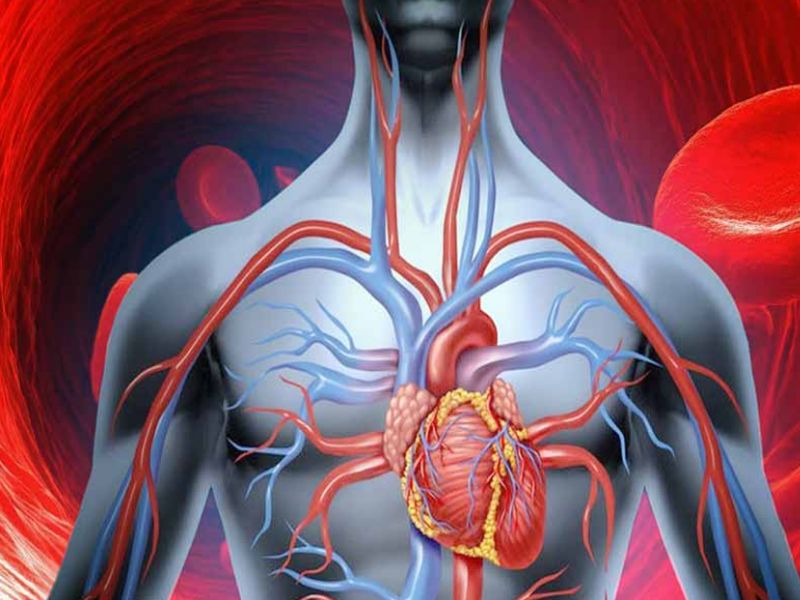

लाइव हिंदी खबर (हेल्थ टिप्स ) :- हार्ट अटैक को बुजुर्गों की बीमारी माना जाता है और धनवानों के दिल की धड़कन की कार्यवाही इस वर्ग से होती है। लेकिन मौजूदा समय के भयानक जीवन-शैली और खाने के कारण, कोरोनरी हार्ट अटैक की इस बीमारी ने हर व्यक्ति को अपना शिकार बनाना शुरू कर दिया है। यह कहा जाता है कि अचानक दिल का दौरा पड़ने वाले व्यक्ति में कोई ऐसा व्यक्ति शामिल होता है जिसे कोई भी व्यक्ति महसूस नहीं कर सकता है। लेकिन यह हमेशा ऐसा नहीं होता है जब वह कोरोनरी हार्ट अटैक से पहले लक्षण और लक्षण प्राप्त करना शुरू कर देता है। आज हम आपको कोरोनरी हार्ट अटैक से पहले के लक्षणों और लक्षणों से अवगत कराने जा रहे हैं ताकि आप उन्हें महसूस कर सकें और यदि आप कभी भी इस प्रकार की समस्या का सामना करते हैं, तो आप पहले से सतर्क हो सकते हैं। इसलिए हमें कोरोनरी हार्ट अटैक की तुलना में पहले लक्षण और लक्षणों का एहसास करने की अनुमति दें।